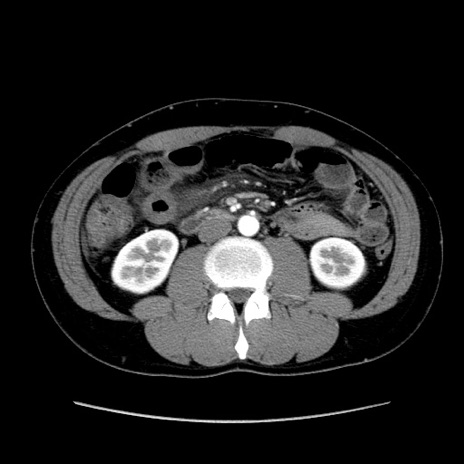

症例36(横断像)

冠状断像

【症例】20歳代 男性

【主訴】心窩部痛

【現病歴】今朝より上腹部痛あり。一旦軽快していたが再度出現したため救急要請。昨日夕に白身の魚を含む刺身を食べた。

【身体所見】BP 136/89mmHg、HR 74/min、BT 37.0℃、腹部:膨満、軟、心窩部に圧痛あり。反跳痛なし、筋性防御なし、腸雑音やや亢進あり。

【データ】WBC 17700、CRP 0.48